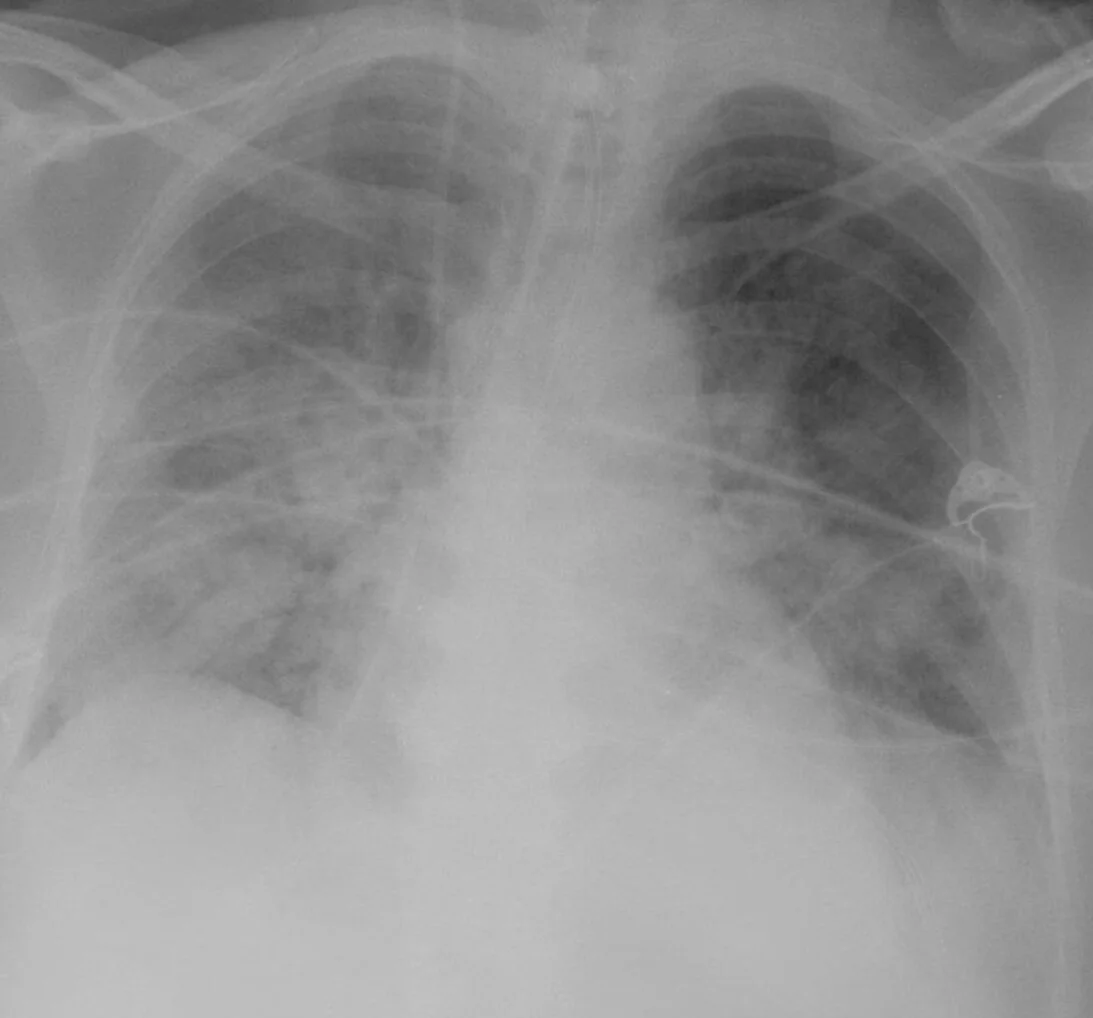

Episode 36 - ARDS Fundamentals I: Classification, Pathophysiology & Initial Vent Management

1. Identify the key diagnostic criteria for ARDS